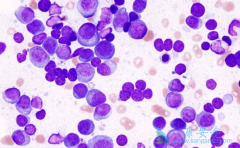

骨髓瘤是骨髓异常浆细胞增多并引起骨髓造血功能衰竭、使骨骼破坏而产生异常增多的单克隆免疫球蛋白为特征的浆细胞疾病。其发病率占据了血液系统疾病的10%至15%,发病率在恶性淋巴瘤之下。常见的临床症状主要包括为骨痛、贫血、高血钙、病理性骨折、压缩 ...

骨髓癌是浆细胞产生的恶性肿瘤,常侵犯多个部位骨髓瘤及组织。 骨髓癌 目前不能治愈,其治疗目标主要是维持生存。所以如何延长骨髓癌患者的寿命就成为了科研人员关注的重点。近期,一项研究表明,在标准的双药疗法中加入硼替佐米可以降低多发性骨髓癌患 ...

多发性骨髓瘤属于血液系统恶性肿瘤,所以如何对疾病进行精确的分期,如何获得更好的化疗疗效就显得非常重要。骨髓瘤细胞是高度分化的B淋巴细胞,增殖活性低,常规的细胞遗传学检查方法敏感性较差。使用常规细胞遗传学检查,可在30%~50%患者的骨髓瘤细胞 ...